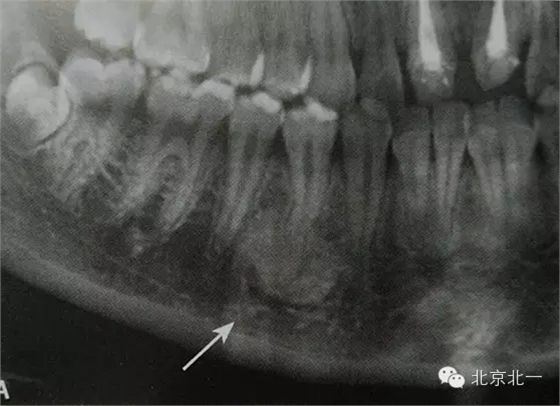

【CBCT表現(xiàn)】:

在CBCT上,根尖型骨島無低密度帶狀影包繞,與周圍骨質(zhì)分界清晰,具有特征性的毛刷樣邊緣,且其發(fā)生區(qū)域的牙根牙周膜影像連續(xù)、完整、不導(dǎo)致頜骨的膨隆。

右下頜C4根尖區(qū)課件一類圓形高密度影,與周圍骨質(zhì)分界清晰,C4牙周膜影像連續(xù)、完整,下頜骨未見膨隆。